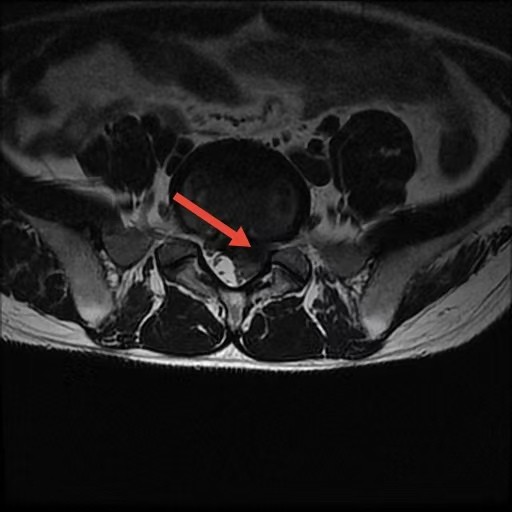

术前

2月7日,我院骨科手术室依旧灯火通明、争分夺秒。手术采用局部麻醉,也摒弃了传统开放手术的长切口,仅在患者腰部打开约1厘米的微小“锁孔”。邱洪九主任团队利用这枚小小的通道,置入脊柱内镜,通过脊柱内镜,清晰定位并精准摘除压迫神经根的“肇事”髓核组织,顺利解除神经压迫、松解受压神经。

整场手术历时仅100分钟,出血量约10毫升,患者全程保持清醒,术后当即感觉腿部麻木、疼痛感明显缓解。该术式为我院成熟开展的后路经椎板间入路腰椎间盘髓核摘除术(PEID),也被形象地称为“锁孔手术”,相较于传统手术,具有创伤小、恢复快、住院时间短等显著优势,特别适用于年轻、急性发作的腰椎间盘突出症患者。